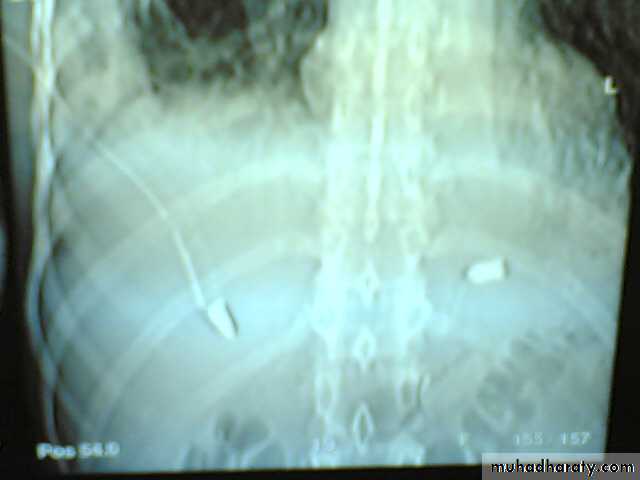

• 7-Diaphragmatic injuries Trauma can lead to rupture of the diaphragm ,most commonly the left side affected ,leading to herniation of the viscera .Stomach is the most frequent organ to herniated followed by the transverse colon , spleen leading to collapse of the lung and mediastinal shift which can be seen on chest X-ray .Barium study is of great help in the diagnosis .Treatment surgery through abdominal , thoracic ,combined approach or by laparoscopy .